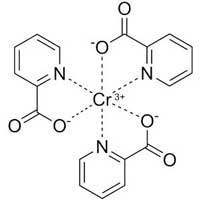

Chromium

Reduces Obesity & Lowers Blood Pressure